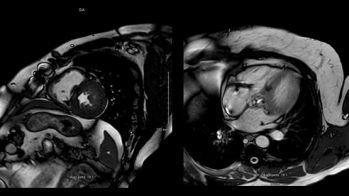

- IRM cardiaque

IRM Cardiaque

Vidéo 5

Vidéo 6

Syndrome de Melas avec atteinte ORL connue + atteinte rénale dyalisé depuis 2022 en projet de Pre greffe rénale.

Découverte d’une atteinte cardiaque associée avec CMH à altération brutale de la FEVG.